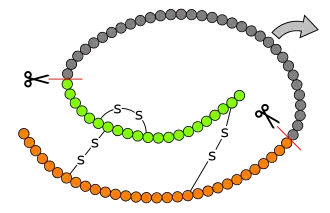

Formation de l'insuline à partir de la proinsuline. La préproinsuline est le produit de l'expression du gène INS et compte 110 résidus d'acides aminés. L'élimination des 24 résidus C-terminaux formant le peptide signal au niveau du réticulum endoplasmique donne la proinsuline, laquelle est convertie en insuline par élimination de 35 résidus entre les chaînes A et B, elles-mêmes réticulées par ponts disulfures. | ||

L'insuline est une hormone constituée de 2 chaînes polypeptidiques reliées entre elles par 2 ponts disulfures et 1 pont disulfure intrachaîne dans la chaine A : une chaîne A de 21 acides aminés, et une chaîne B de 30 acides aminés. La structure de l'insuline a été déterminée par Frederick Sanger. Ce fut l'objet du premier de ses deux prix Nobel, en 1958. La structure de molécules de plus en plus complexes peut être analysée, jusqu'à ce que, grâce à ses travaux sur la détermination par les techniques des rayons X Dorothy Crowfoot Hodgkin résolve enfin la structure de l'insuline, ce qui lui vaudra le prix Nobel de Chimie en 1969. L'insuline est produite par les cellules β des îlots de Langerhans du pancréas sous la forme d'une pré-pro-insuline constituée d'une seule chaîne peptidique, dont deux fragments, le peptide signal (23AA N-ter) est éliminé par l'action d'une enzyme, la signal peptidase qui va cliver le peptide signal entraînant la création des trois ponts disulfures, on obtient la pro-insuline qui subira l'élimination du peptide C par une autre enzyme, la PC1, ce qui va libérer un fragment central, tandis que les deux chaînes néoformées vont rester associées grâce aux ponts disulfures : enfin l'extrémité C-Terminale d'une des chaines va être clivée par l'action d'une carboxypeptidase E (CPE) pour devenir l'insuline sous sa forme mature, et donc active. La proinsuline a une structure très voisine de celle des deux principaux facteurs de croissance, IGF-1 et IGF-2, et des concentrations élevées de ces hormones permettent des effets biologiques par signalisation après liaison aux récepteurs des autres : hypoglycémie lors de sécrétion massive d'IGF-1 et d'IGF-2 par des tumeurs. L'insuline circule à des concentrations de l'ordre de la nanomole par litre.